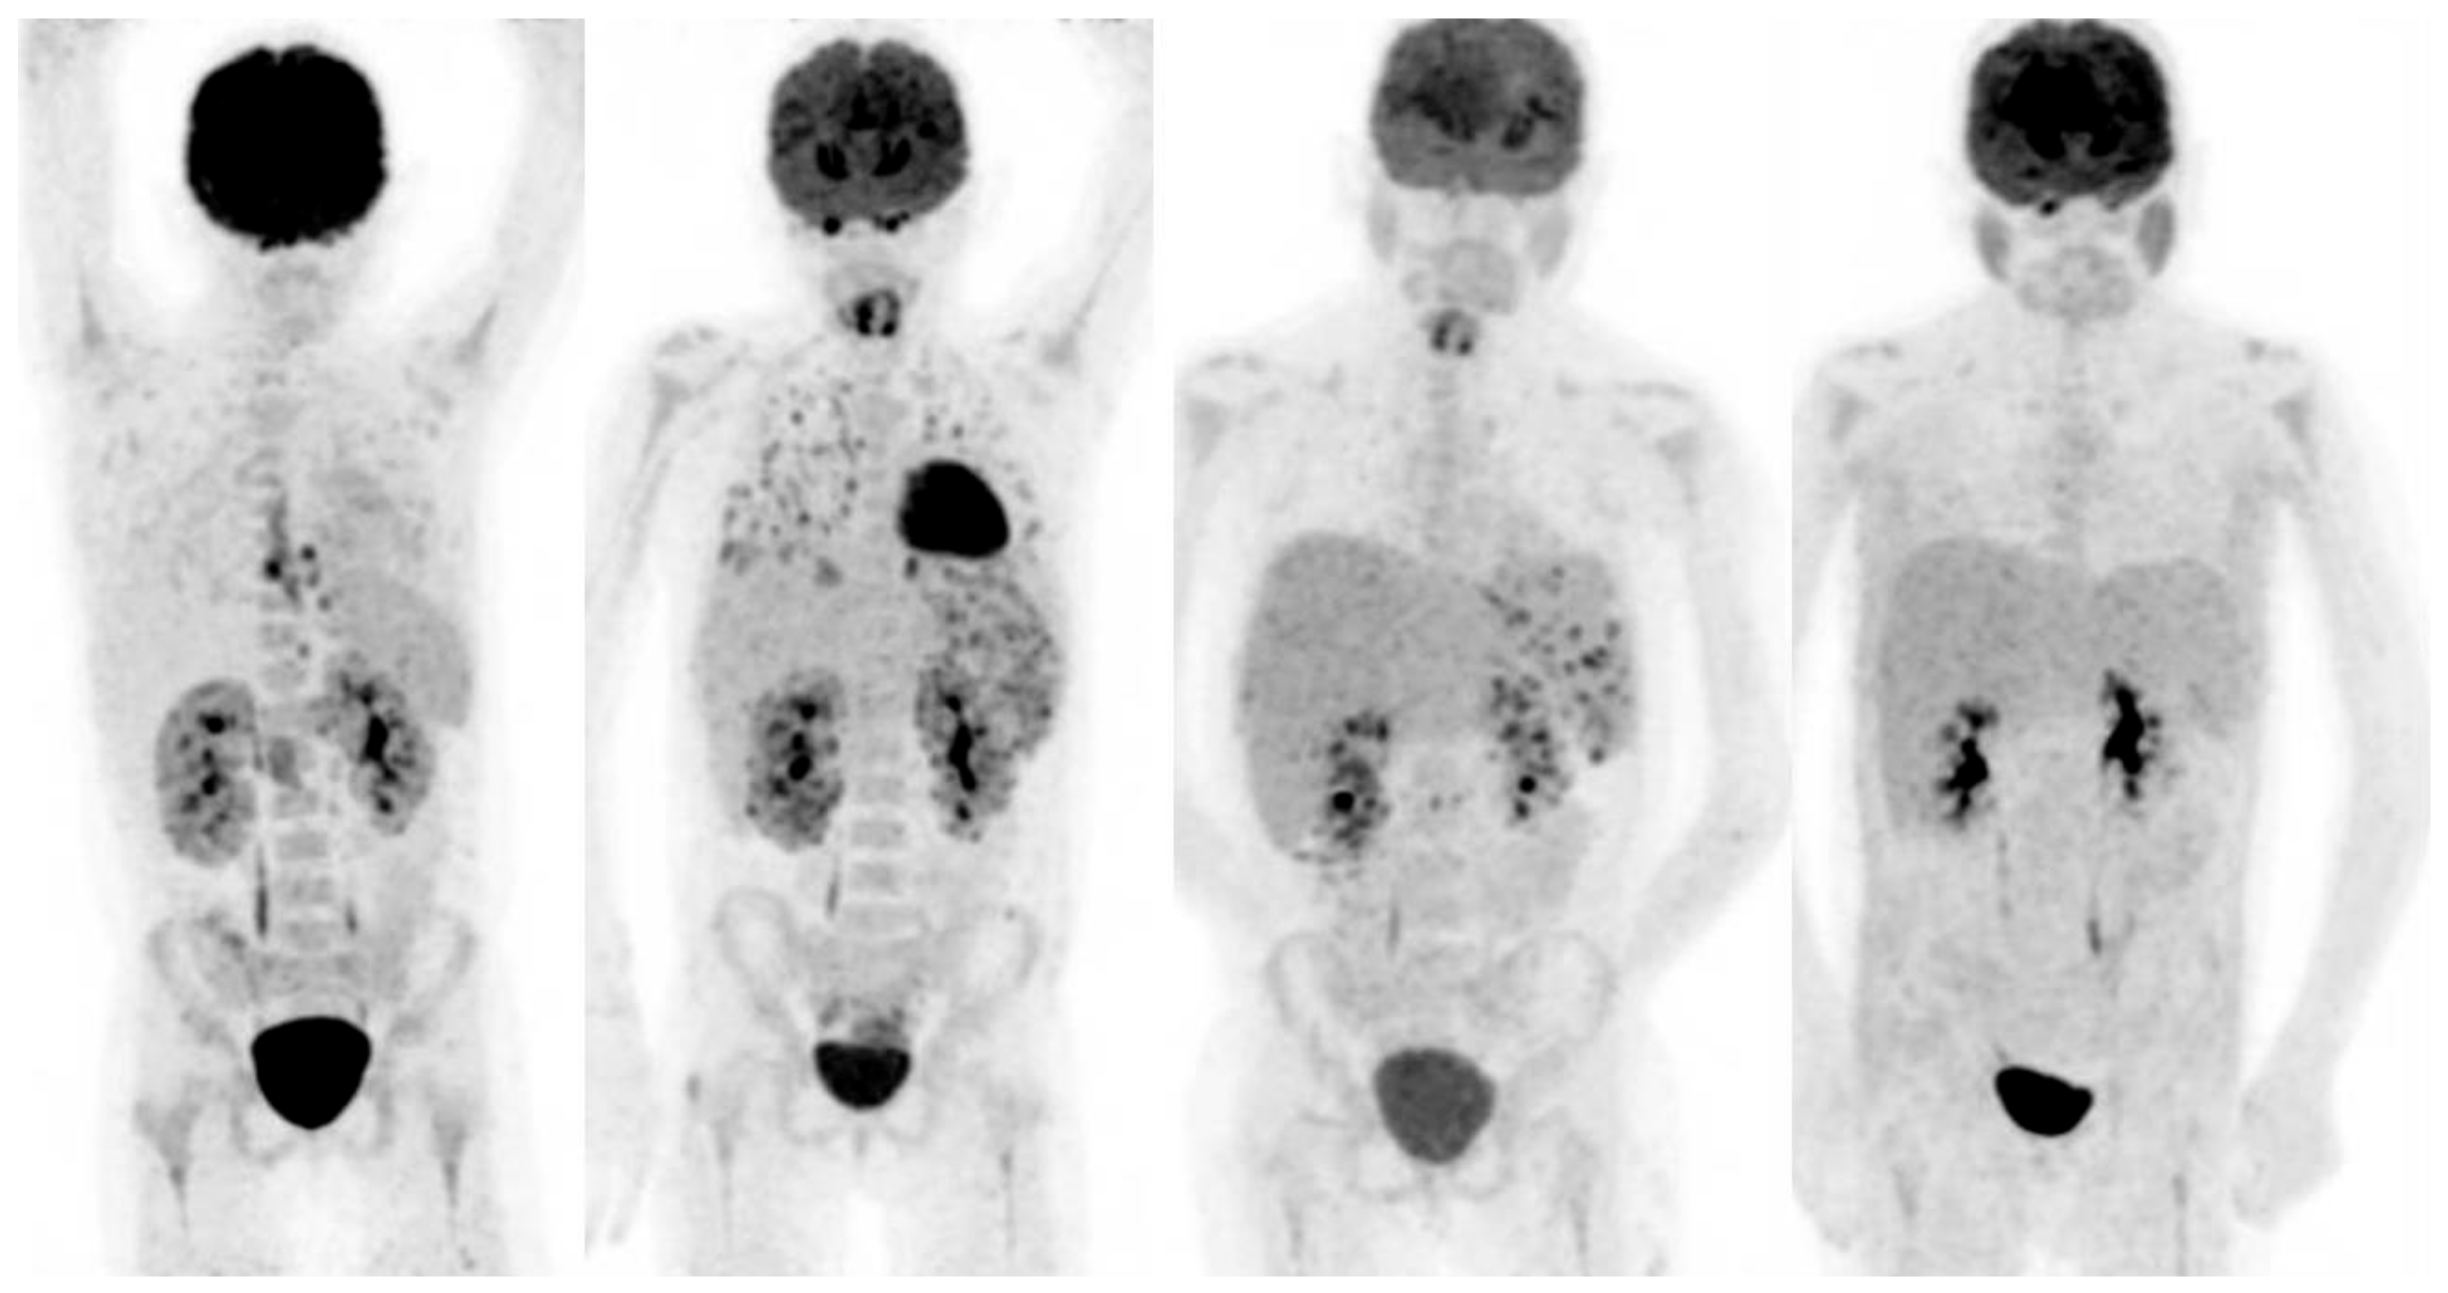

- Markovic SNGalli, F.; Suman, V.J.; Nevala, W.K.; Paulsen, A.M.; Hung, J.C.; Gansen, D.N.; Erickson, L.A.; Marchetti, P.; Wiseman, G.A.; Signore, A. Non-invasive visualization of tumor infiltrating lymphocytes in patients with metastatic melanoma undergoing immune checkpoint inhibitor therapy: A pilot study. Oncotarget 2018, 9, 30268–30278. [Google Scholar] [CrossRef]